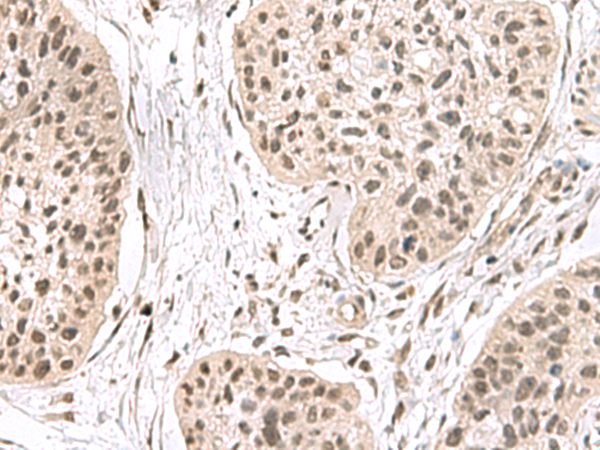

IHC positive control: |

Human esophagus cancer |